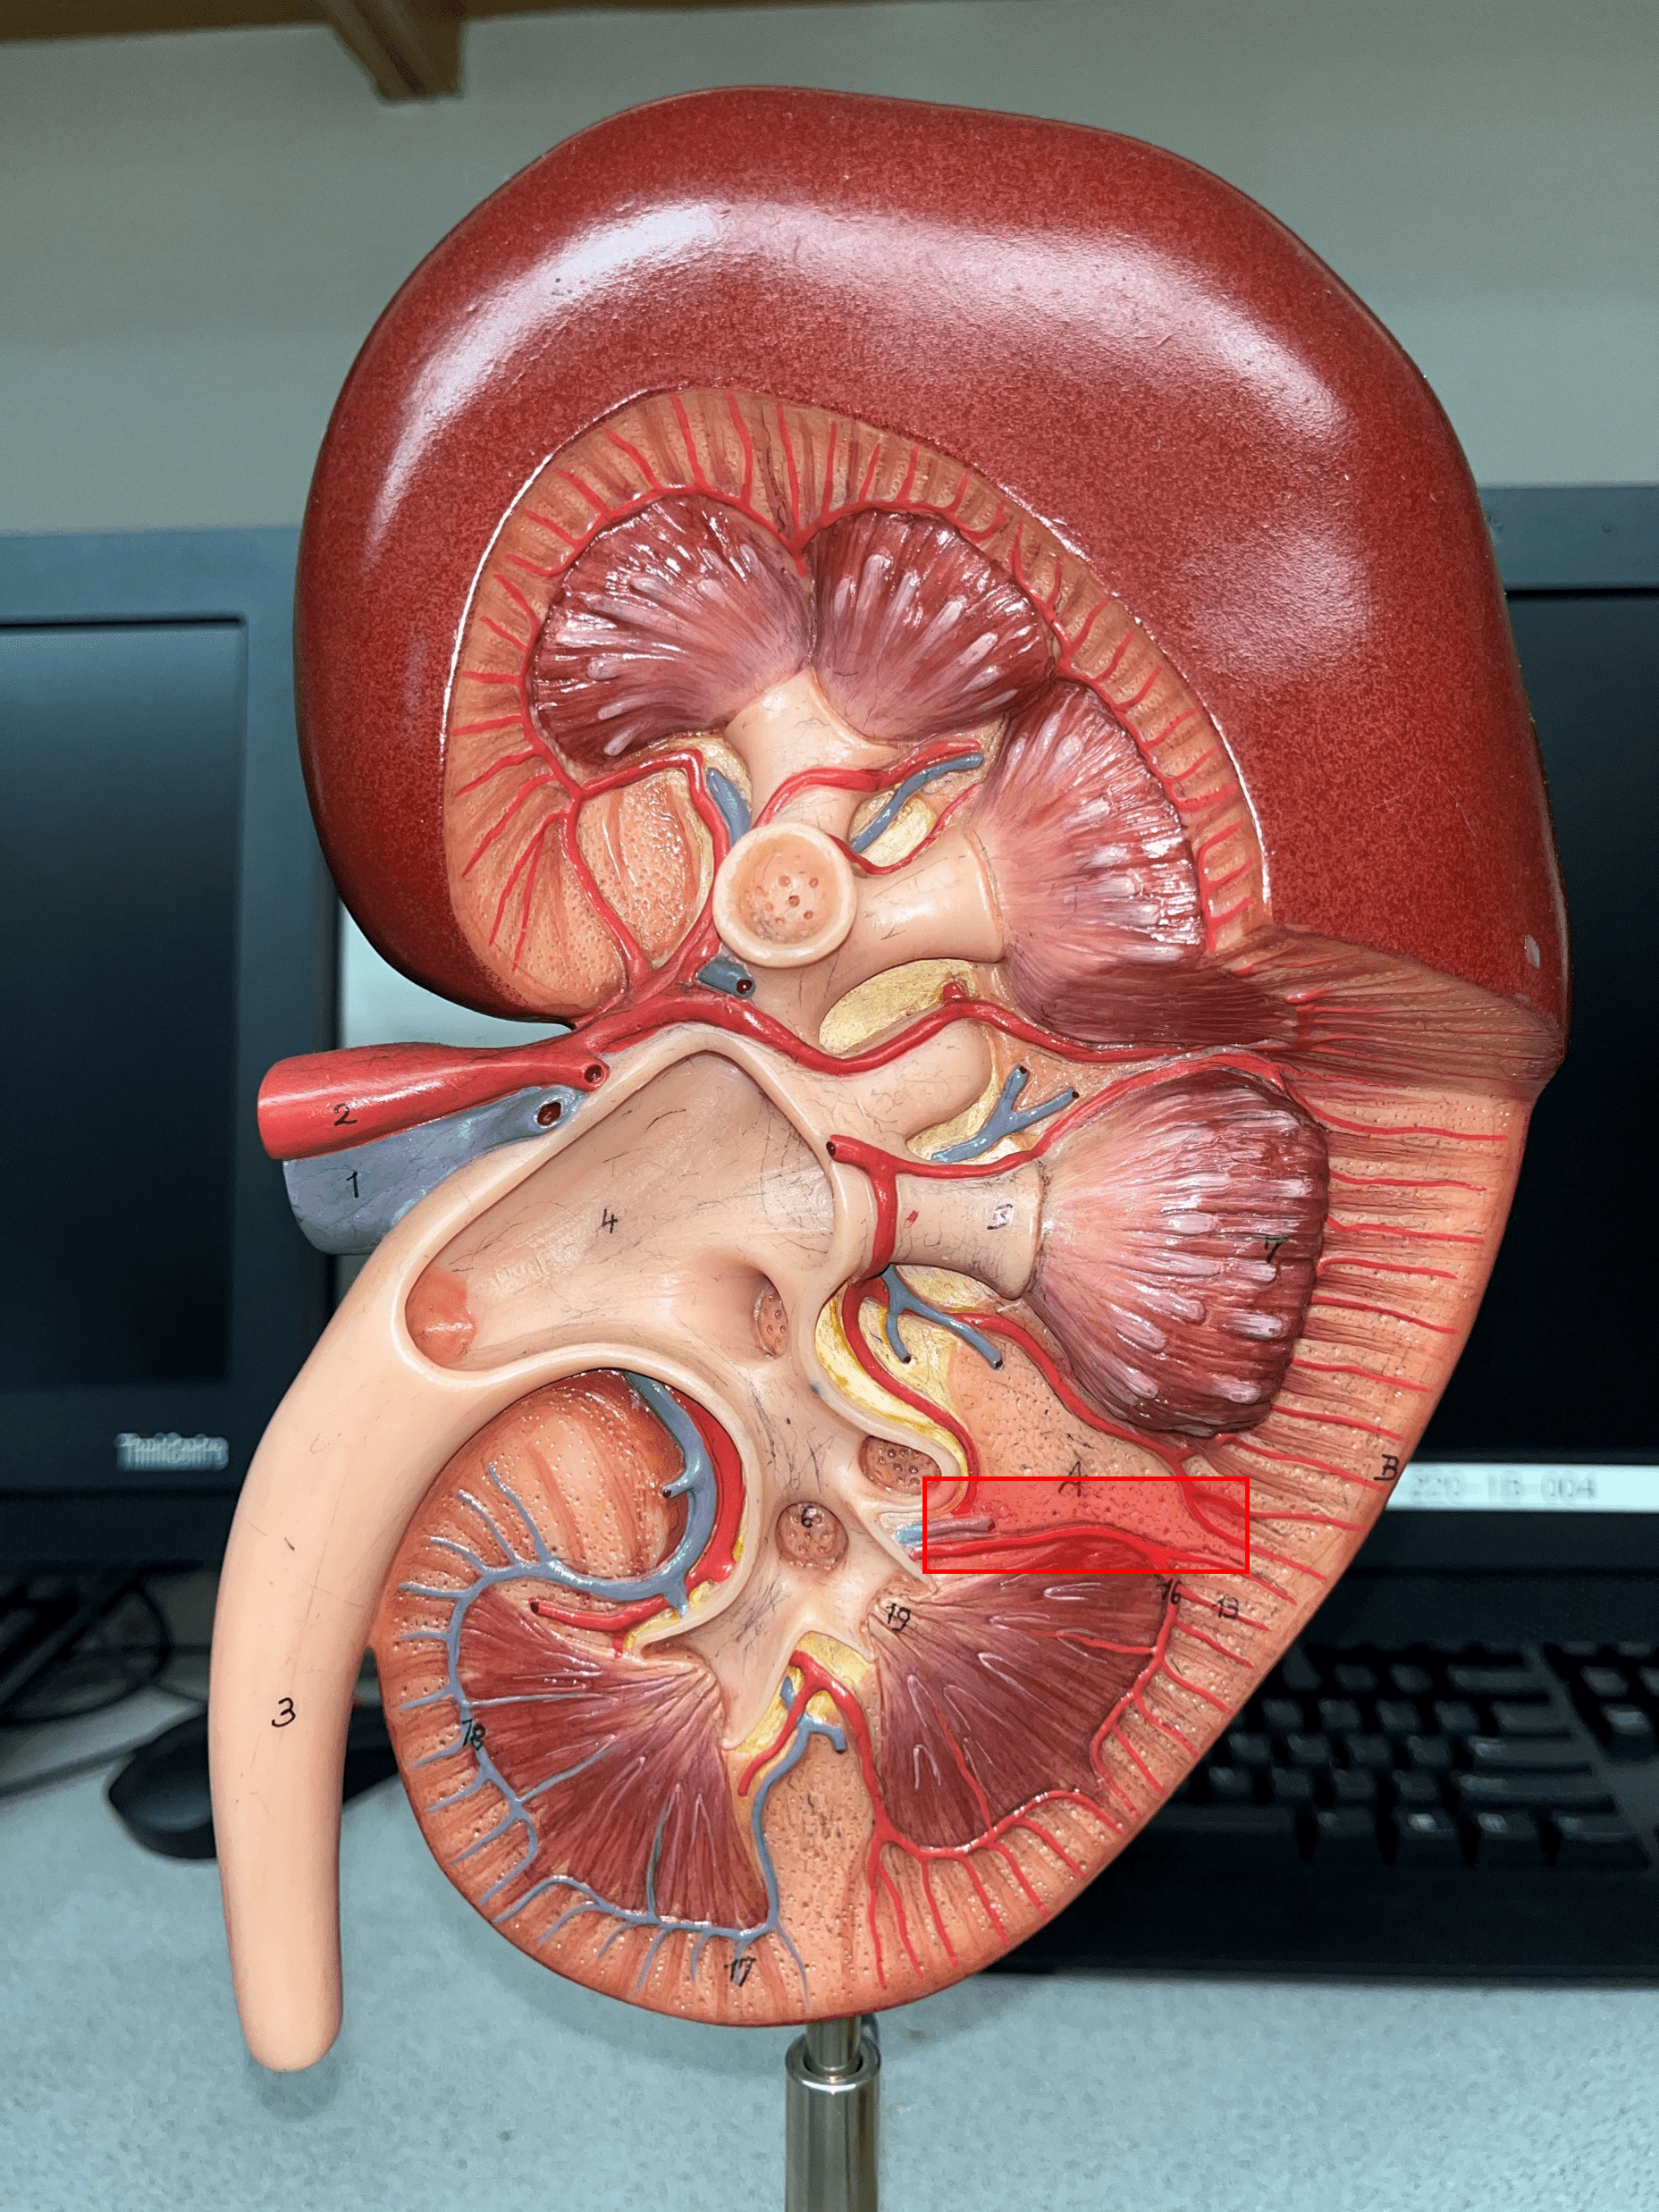

arcuate artery

• Extends along the base of the renal pyramids.

• Branches of an interlobar a.

• Branches into smaller interlobular aa.

• Branches of an interlobar a.

• Branches into smaller interlobular aa.

interlobular artery

• Extends through the renal cortex.

• Branches of an arcuate a.

• Branches into an afferent arteriole of a glomerulus.

• Branches of an arcuate a.

• Branches into an afferent arteriole of a glomerulus.